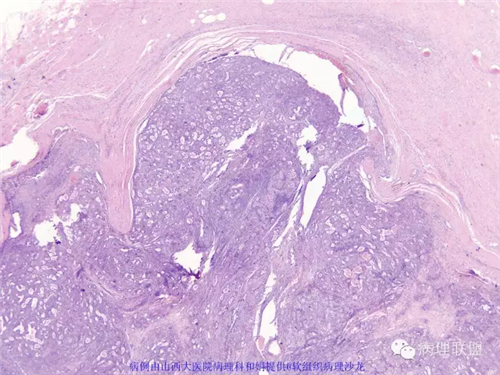

M,57岁,右膝关节外侧皮下肿物10余年,活动度好。

本例形态学上是非常典型的双相型滑膜肉瘤,滑膜肉瘤临床上大部分表现为生长缓慢的肿瘤。以青壮年多见,主要发生于四肢大关节附近,也可见于其他少见部位,如肺、肾等实质器官,形态学分为5种类型:单相纤维型、单相上皮型、双相型、低分化梭形细胞型和小细胞型。有文献报道个别患者有长达20年的病史。